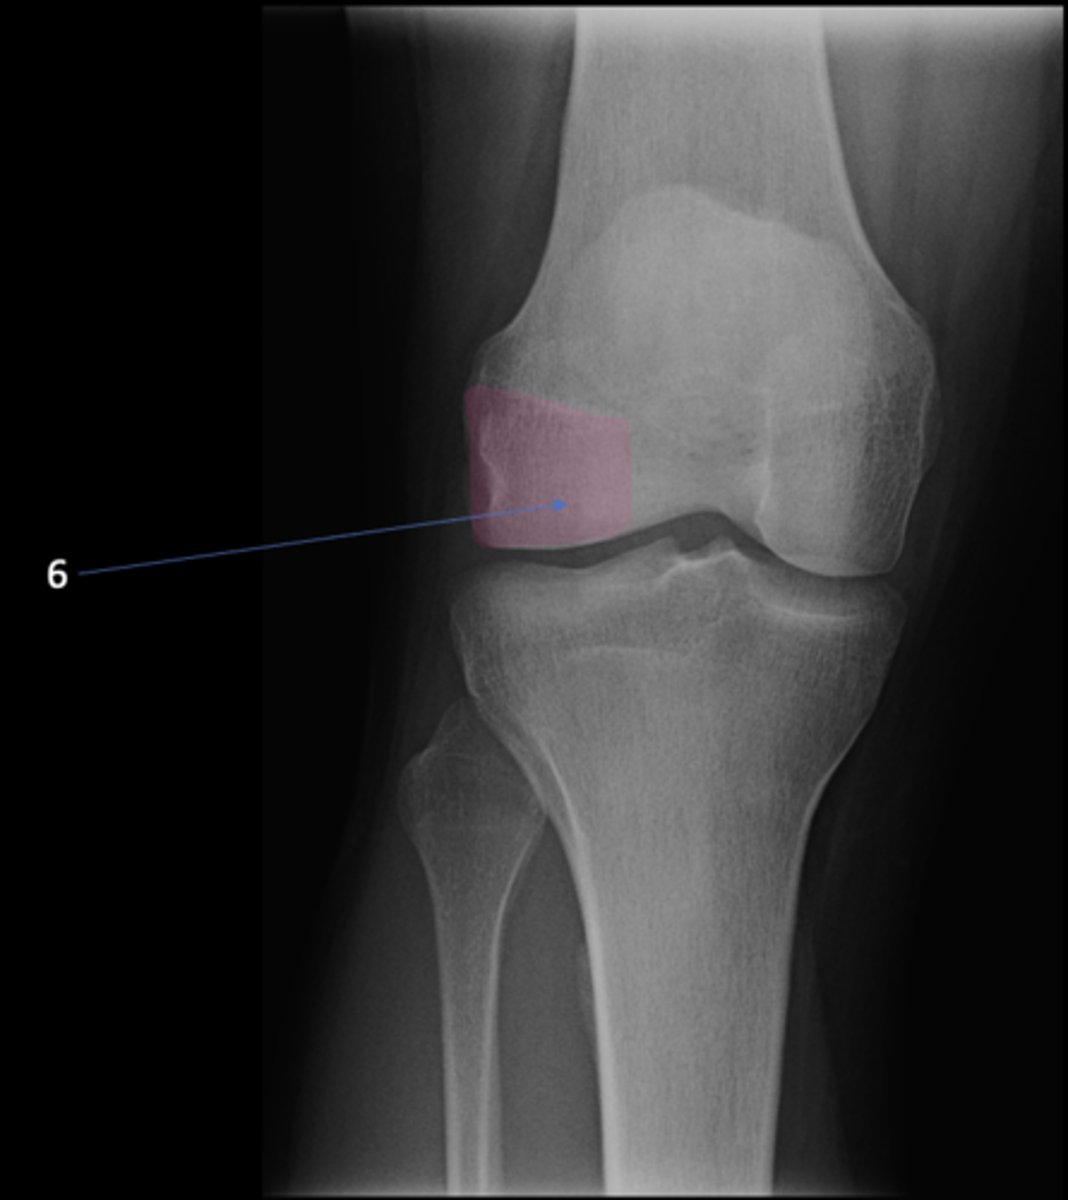

AP knee

View?

<p>View?</p>

49

New cards

Fibular head

ID 1

<p>ID 1</p>

50

Apex of fibular head

ID 2

<p>ID 2</p>

51

Fossa for popliteal tendon

ID 3

<p>ID 3</p>

52

Intercondylar eminence

ID 4

<p>ID 4</p>

53

Superior aspect of patella

ID 5

<p>ID 5</p>

54

Lateral femoral condyle

ID 6

<p>ID 6</p>

55

Medial femoral condyle

ID 7

<p>ID 7</p>

56

Intercondylar fossa

ID 8

<p>ID 8</p>

57

Apex of patella

ID 9

<p>ID 9</p>

58

Lateral femoral epicondyle

ID 10

<p>ID 10</p>

59

Medial femoral epicondyle

ID 11

<p>ID 11</p>

60

Tibial tuberosity

ID 12

<p>ID 12</p>

61

Medial tibial plateau

ID 13

<p>ID 13</p>

62

Lateral tibial plateau

ID 14

<p>ID 14</p>

63

Medial tibial condyle

ID 15

<p>ID 15</p>

64

Lateral tibial condyle

ID 16

<p>ID 16</p>

65

Physeal scar

ID 17

<p>ID 17</p>

66

Adductor tubercle

ID 18

<p>ID 18</p>

67